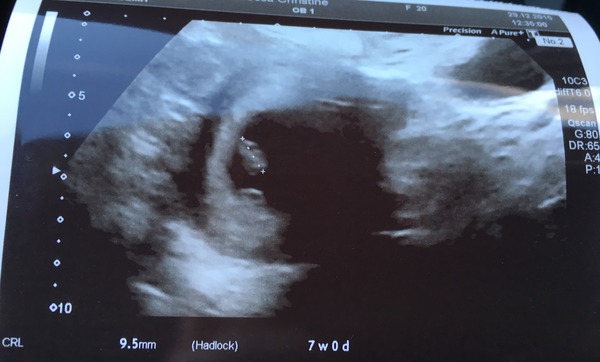

Christinedonna · 29/12/2015 15:01

7 weeks. Little bean with a flickering heart beat

Congratulations Christine! Was that by external or dildocam? Wink.

Thank you! That was external (first time we've had any luck with it)